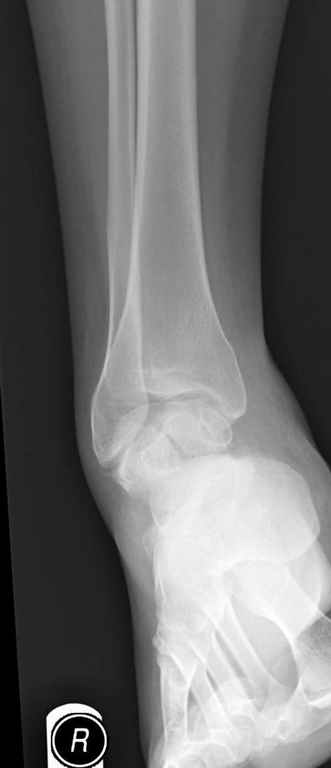

Уважаемые участники русского Ортофорума, поздравляю всех со всеми прошедшими праздниками: Новым годом, Рождеством, Hanukkah, Kwanzaa, желаю участникам всего наилучшего и здоровья.Повреждение таранной кости.Больной 81г автоавария, повреждение таранной кости, здесь снимки. Какие рекомендации?Djoldas Kuldjanov, MDDepartment of Orthopedic SurgerySt. Louis University Medical Center

Вдогонку по поводу перелома таранной кости, больная 81, не страдает диабетом, перелом закрытый, в первый же день поступления ограничились временным наружным фиксатором (как на снимке).

За пару недель насчитал 5 больных с переломом таранной кости, из них двое с двусторонним повреждением.

Из-за отека на стопе тактика лечения у всех была

одинаковая: временная наружная фиксация до спадения отека, при изолированных переломах они выписывались домой и через дней 7 госпитализировались на оперативное лечение.

Примеры на снимке...